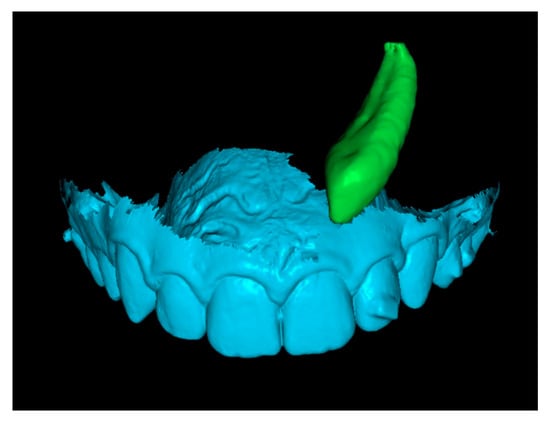

Fourth step: Overlap the Initial Canine with the Crown of the Canine in the Final STL.

Since the final STL does not include tooth roots, only the crowns of the initial and final canines were overlapped. This alignment positioned the canine in its final position after traction. In some cases, after overlapping, the apex of the canine was not visible (Figure 8). When this occurred, a small cut was made to enable visualization of the apex.

Figure 8.

Overlay of canine in initial and final positions.

Fifth step: Displacement Measurements.

The previous models of the initial and final canines were isolated and saved as separate STL files. Displacement measurements of the cusp and apex were then performed using the RealGUIDE 5.3® software (Figure 9). All evaluations and measurements were performed in a blinded manner, with the primary evaluator unaware of patient identities throughout the study. The entire assessment process was conducted by a single author and was continuously supervised and reviewed by a second author. A high level of agreement was consistently observed, supporting the reliability of the methodology.

Figure 9.

Cusp and apex displacement measurements.